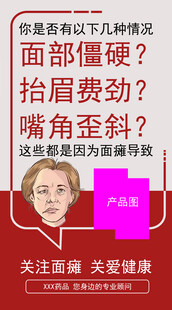

面瘫问题 面部僵硬 面部抽搐 共享分:100

面瘫问题 面部僵硬 面部抽搐 共享分:100 -